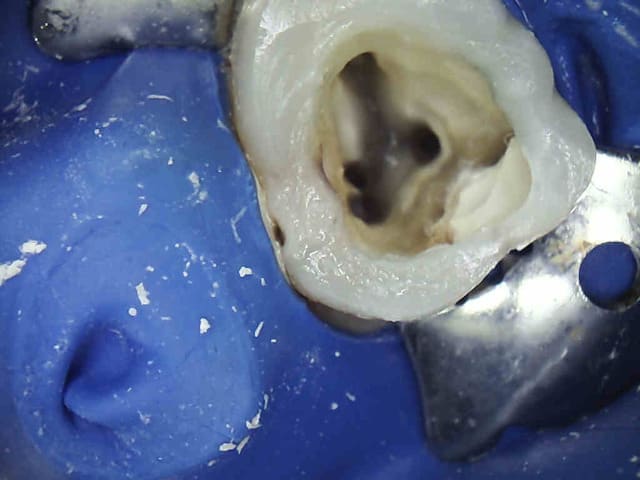

C'est sur. 1H pour 2 endos molaires c'est chaud, on finit par faire des conneries-))))

En espérant qu'ils soient en Y comme la 7.

3 ezcjhg - Eugenol

4 w0fyb0 - Eugenol

5 hb1jpv - Eugenol

6 qrlsxe - Eugenol

7 g5aq0k - Eugenol

8 cyv9ae - Eugenol

9 kvtqqw - Eugenol

les endos sont chouettes.

je suis encore pour ma part pas mal long quand il s'agit d'endo.

sinon c'est quoi le truc entre la 5 et la 6.

Wed jet. Ca se pose avec une pince.

R25 + digue ca fait gagner du temps. Ceci dit dans ce cas j'ai un peu grillé les étapes ( forcé) D'ou le faux canal sur le ml de 46.